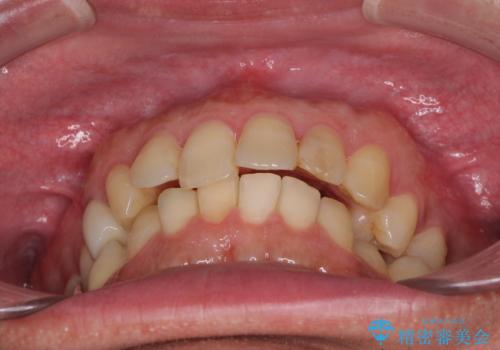

外側に飛び出した歯 インビザラインによる矯正治療

- 外に飛び出した側方の歯と、前歯のデコボコを気にして来院された患者様です。

IPR(歯と歯の間を削る)によってデコボコが解消するように設計し、インビザラインにより治療を行うこととしました。